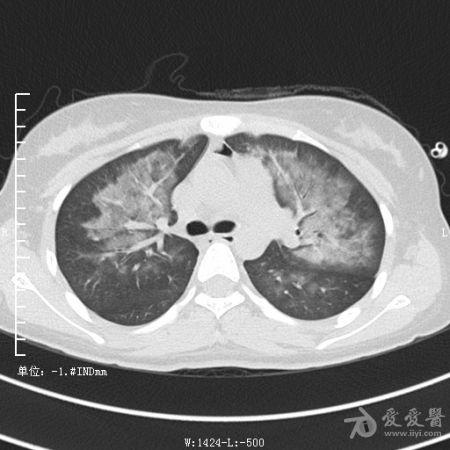

典型支气管扩张及肺水肿CT片

典型支气管扩张肺水肿